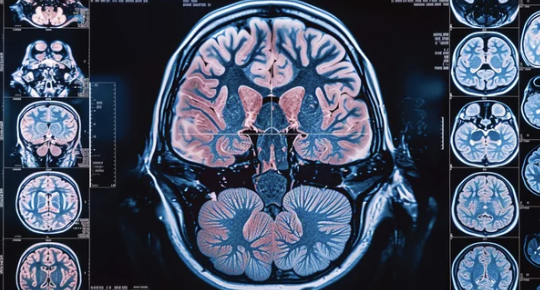

안녕하세요, 여러분의 건강을 소중히 생각하는 건강 지킴이입니다. 😊 오늘은 '침묵의 살인자'라고 불리는 뇌출혈에 대해 알아보려고 합니다. 뇌출혈은 뇌혈관이 터져 뇌 조직에 혈액이 유출되는 질환으로, 심각한 후유증을 남기거나 생명을 위협할 수 있습니다.

뇌출혈은 뇌혈관이 터져 뇌 조직에 혈액이 유출되는 질환입니다. 뇌출혈의 주요 원인은 다음과 같습니다.